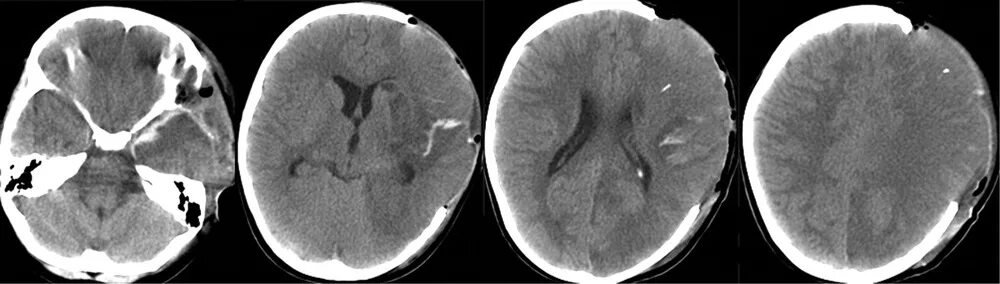

50 лет кт